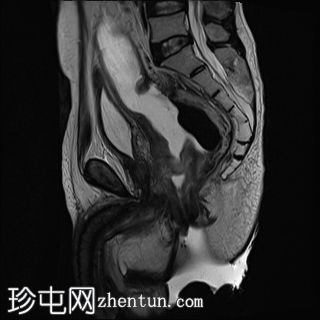

轴位

T2加权像

直肠下三分之一处可见一段弥漫性不规则肠壁增厚,伴浆膜外延伸,在右前外侧壁形成“C”形肿块,增强后呈不均匀强化,中央可见坏死。

左侧外侧壁和后壁可见大片缺损,内含气体和粪便,被不规则增厚的肠壁包裹。该缺损在T1加权像上呈低信号,在T2加权像上呈高信号,并伴有明显的扩散受限。

可见肠系膜脂肪间隙条索状改变和水肿。